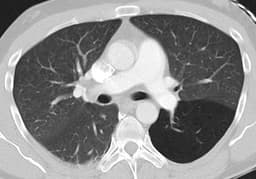

- The nexus chest CT scan rule is based on an 11,000 subject, multicenter study that looked for signs following a trauma that predicted significant findings on subsequent chest CT.

- Findings that were associated with abnormal chest CT included: abnormal CXR, distracting injury, chest wall, sternal, thoracic spine or scapular tenderness. Furthermore, a mechanism of injury that includes rapid deceleration was also associated.

- If a patient has none of the above findings, then there is only a small chance that there will be an abnormal chest CT.